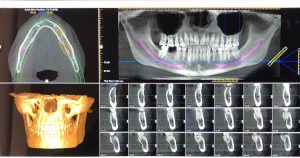

Antes de realizar la cirugía, la Directora y experta en implantología dental, Dra. Teruelo de Luis, realiza un estudio pormenorizado para evitar problemas futuros y garantizar las máximas posibilidades de éxito. Para ello, realiza una exploración radiológica completa de modo que puede ver las condiciones del hueso donde serán colocados los implantes y realiza modelos de registro para tener en cuenta todas las variables existentes.

En InterORALIA prestamos especial importancia a la planificación cuando se va a realizar un tratamiento de implantología, ya que cada paciente tiene unas características y condiciones bucodentales diferentes. Por eso, realizamos un estudio personalizado y minucioso de la boca del paciente para maximizar el éxito del tratamiento.

Lo primero que se hace antes de poner un implante dental es el diagnóstico. En el diagnóstico revisamos el estado del hueso y la encía y evaluamos todas las variables para poner el implante dental de la mejor manera posible.